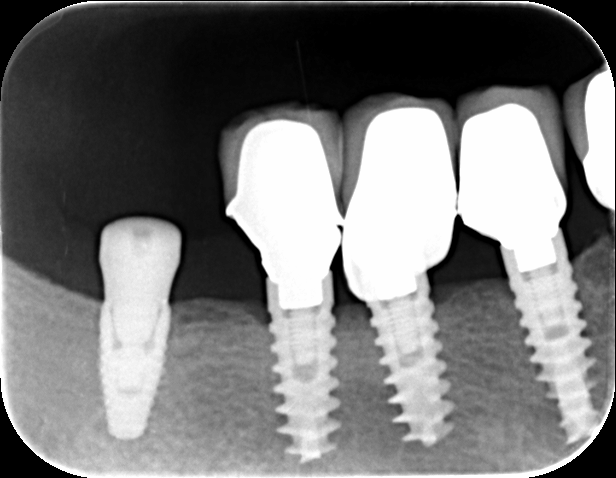

Hola, nos gustaría saber que implante podría ser el de la posición 12. Este Paciente fue tratado en Vitaldent del sector 1 y presenta implantes 3i en posterior. Respecto al [...]

Paciente de 68 años con impantes en 4º cuadrante que al realizarle la extracion del 47 ha saltado parte de la corona del implante del 46. Necesito saber que tipo [...]